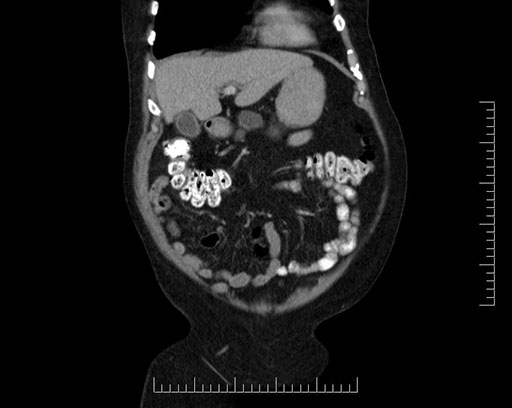

Whipple (pancreaticoduodenectomy) [case 7]

Coronal - stented